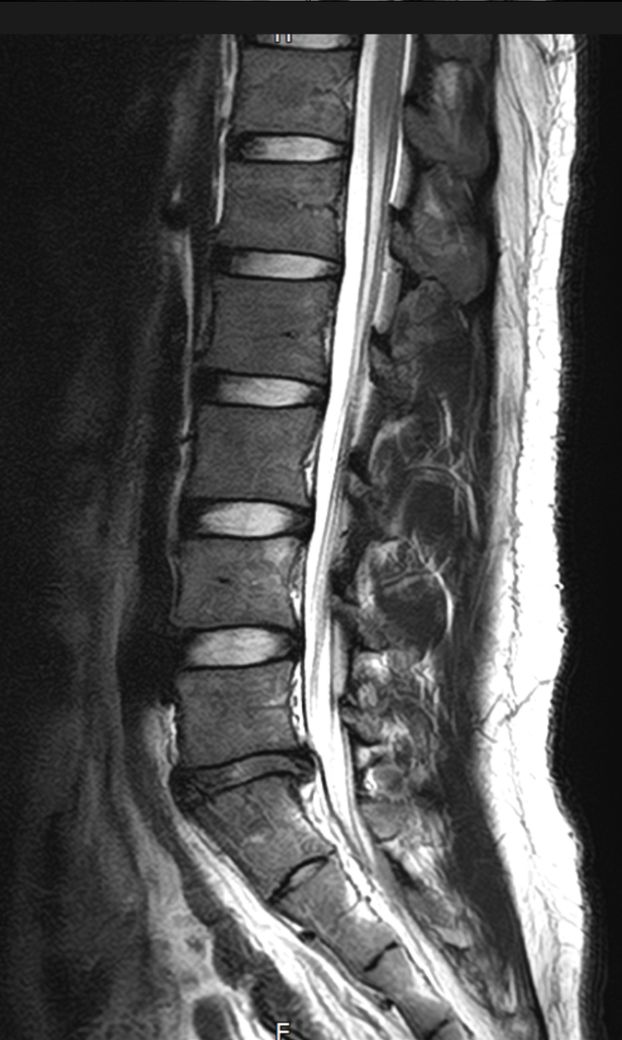

허리 삐끗후 mri 촬영하여 cd만 받고 진료는 좀 뒤로 밀려서 궁금한 마음에 사진 올립니다 ㅜ

먼저 cd 열어보니 사진이 여러개 있던데 대충 사진 보는 법 구글링해서 몇개 추출한거라 단면 같은건 잘못된 걸 고른걸 수도 있어서 양해 부탁드립니다 ㅜ

1. 현재 평소에는 큰 통증은 없지만 오래 걷거나 앉으면 허리가 뻐근해집니다... mri상 상태가 많이 심각한가요?

2. 한국나이로 27살인데 진로 준비로 고등학생때부터 앉아있는 시간이 정말 긴편이라 약간의 허리통증은 항상 있었습니다. 현재 나이에 비해 퇴행성 변화?는 많이 심각한가요? 3~40대에 심각하게 아플까봐 걱정입니다 ㅜ

요추5번 - 천추1번 사이의 디스크에 탈출증이 있으시네요.

나이에 비해서 디스크간격도 좀 좁아져있는 상태입니다. 지금 허리가 아프신것도 다 디스크가 원인이겠습니다.

이야기 하신것과 같이 오래 허리를 굽힌 상태로 앉아있는 생활이 이 디스크탈출의 원인이겠습니다.